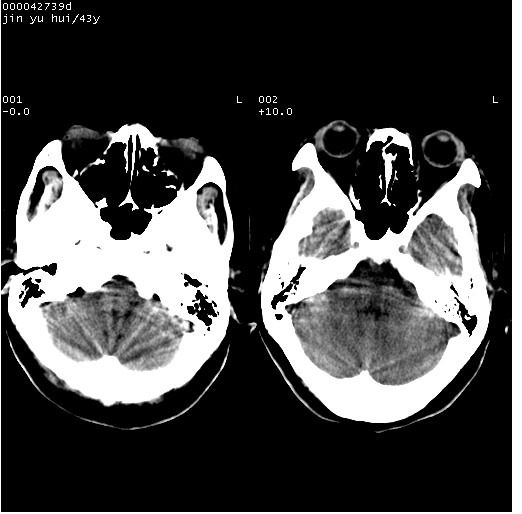

患者 女,43岁。头部外伤26天,经住院治疗,现头痛减轻。申请ct复查,了解颅内情况。

临床诊断:2级脑外伤。

颅脑ct轴位平扫(层厚、层距均为10mm),图像如下: